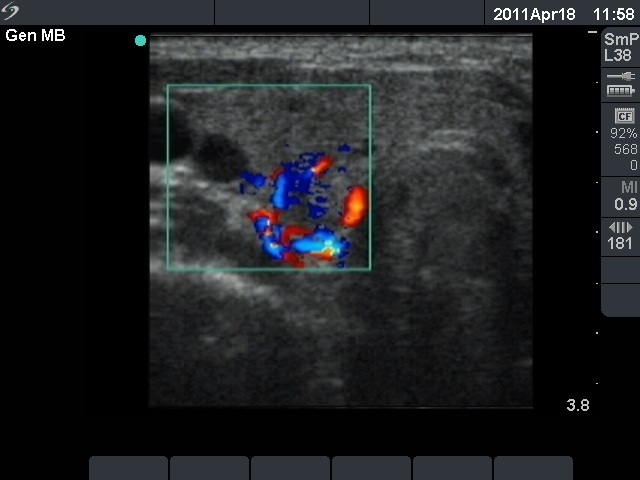

Ultrasonography: The right thyroid was echonormal and contained several small, insignificant lesions. There was a hypoechogenic lesion with blurred borders in the central and in the ventro-medial part of the left thyroid with increased intranodular blood flow.

The ultrasound pattern of de Quervain's thyroiditis and that of papillary cancer are very similar: a hypoechogenic lesion with blurred borders are found in both cases. They differ in vascularization statistically but the vascular pattern has only limited practical significance. In the acute phase of de Quervain's thyroiditis the vascularization is generally decreased but even in this case the situation was the opposite. The finding of not one but multiple hypoechogenic areas favored the possibility of subacute thyroiditis.